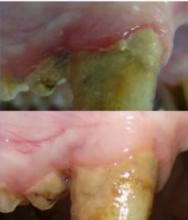

PARODONTITE: Le composé qui résorbe l'inflammation en quelques semaines